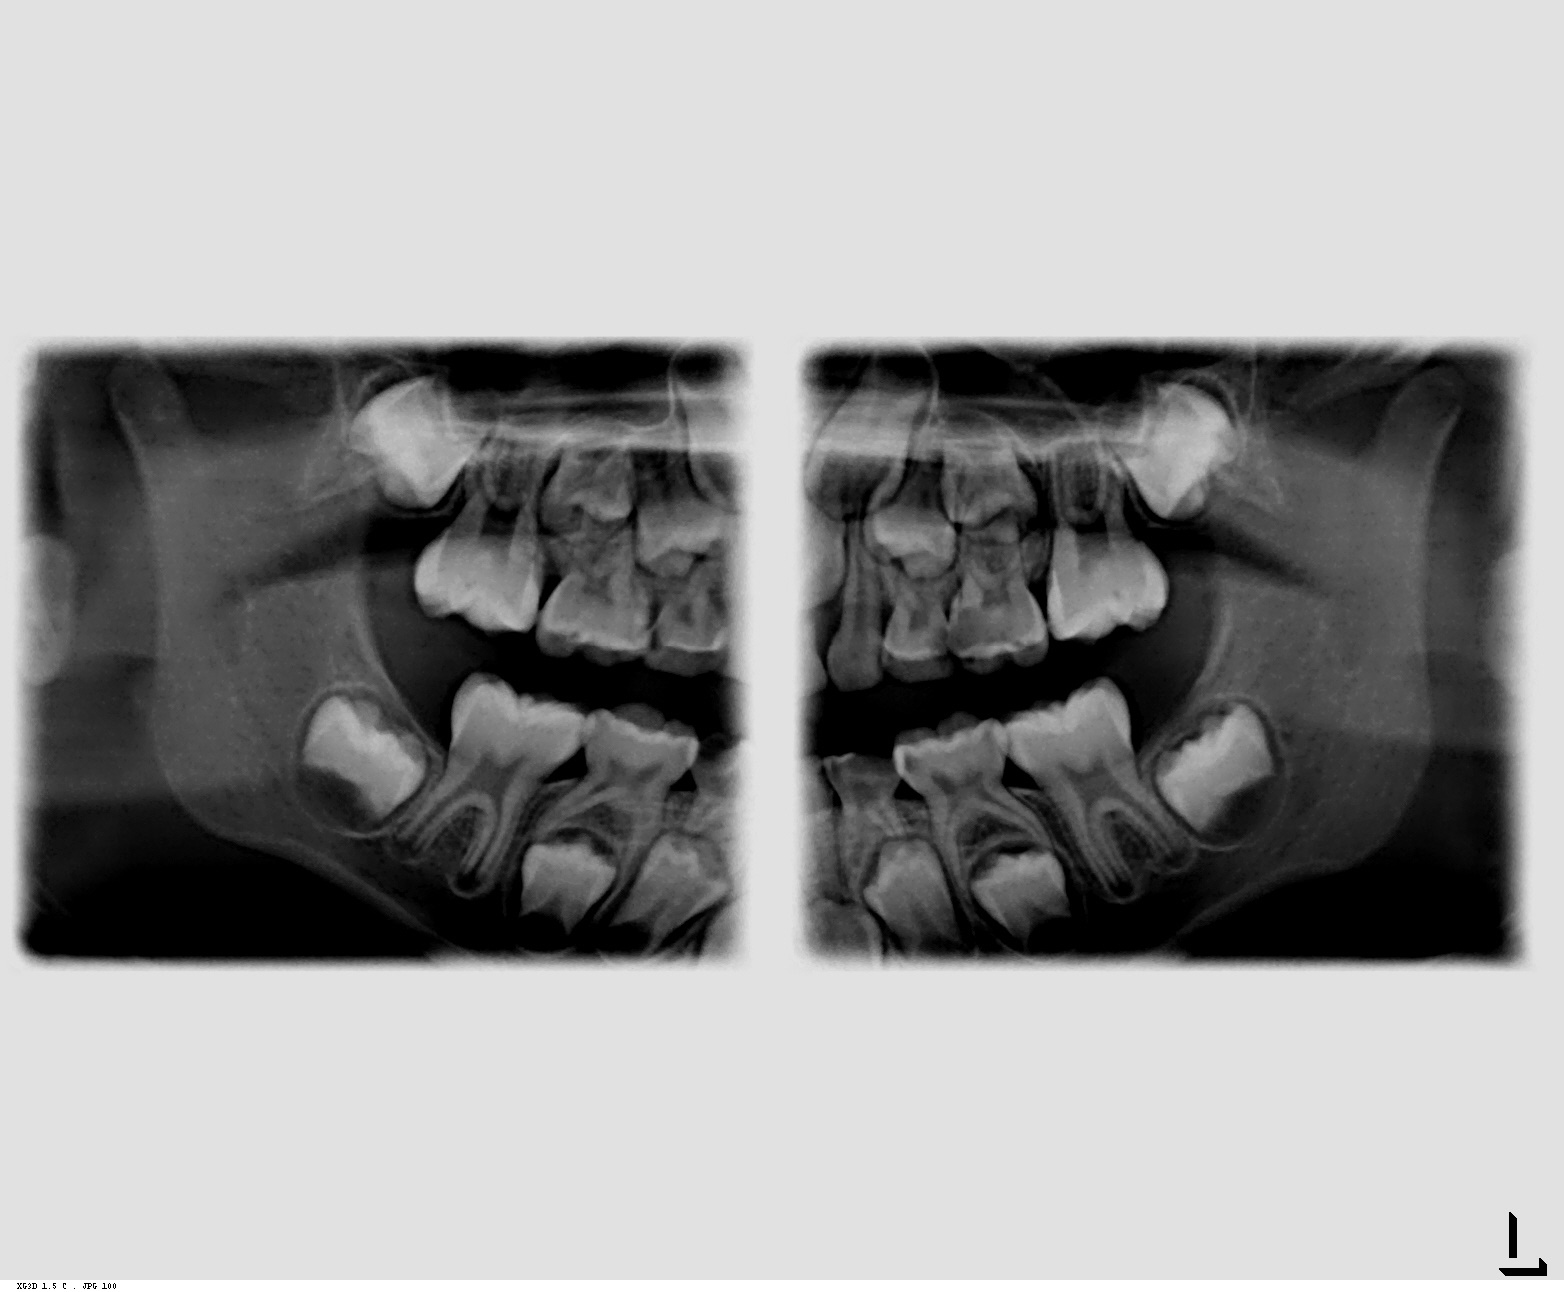

Panorâmica

A Radiografia Panorâmica nos dá uma visão geral dos maxilares, sendo utilizada em todas as especialidades. Nesta incidência, observam-se:

- dentes presentes, presença de cáries extensas, processos patológicos no periápice.

- grau de desenvolvimento dental, posicionamento dos dentes, a relação do dente permanente com o dente decíduo, presença de patologia do folículo.

- presença de reabsorções ósseas alveolares.

- característica do trabeculado ósseo da maxila e mandíbula.

- posicionamento dos reparos anatômicos.

- pesquisa de raízes residuais, fraturas ósseas, patologias.

- acompanhamento de tratamentos endodônticos e ortodônticos.

- preservação de tratamentos cirúrgicos